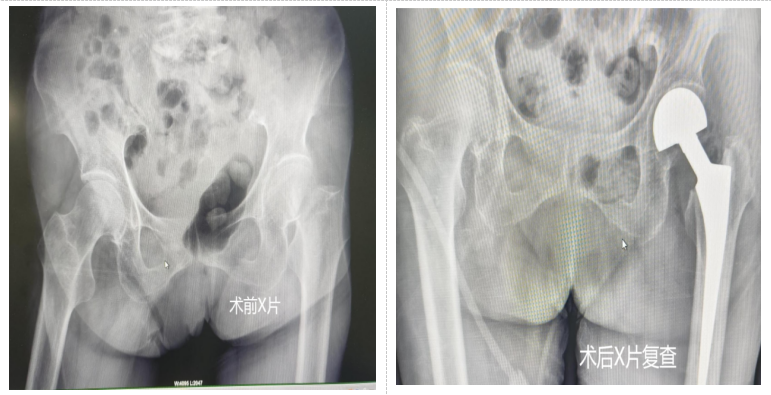

据悉,该百岁老人因摔倒致左股骨颈骨折,剧痛无法行走。考虑患者年事已高,手术危险性极大,若不进行手术,长期卧床将导致多种并发症,严重影响生活质量乃至危及生命。医院骨科团队经详细评估、多科室会诊,并与家属充分沟通后,最终确定实施人工髋关节置换术。

手术中,骨科团队与麻醉科无缝协作,以最优方案在最短时间内完成操作,将手术创伤与出血降至最低。术后,老人在骨科病房接受全方位监护与系统化康复治疗,为次日早期下床、重获行动能力筑牢基础。